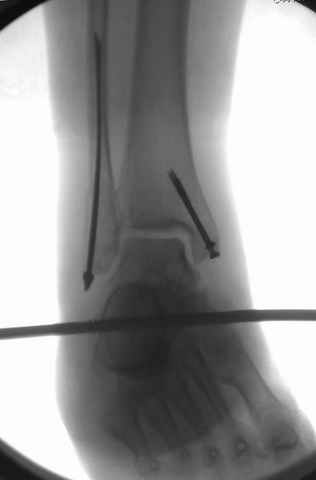

After some days of traction I would like to insert an external fixator (I think a circular one instead of a monoaxial one, because of the multiplanar situation of the fracture).

I would put simple unilateral, medially positioned external fixator (two pins in calcaneus - not to violate talus needed for later fusion, two in tibia), allow soft tissues to recover and in 2-3 weeks I would do delayed ankle fusion.

What sort of traction is he on? Why not a circular fixator straightaway incorporating the foot?

I agree with primary spanning ex-fix, but IMHO some days later it is worth to attempt to restore tibial articular surface as much as possible, using ligamentotaxis and joystick wires under image intensifier. Maybe even put autografts through limited incisions.